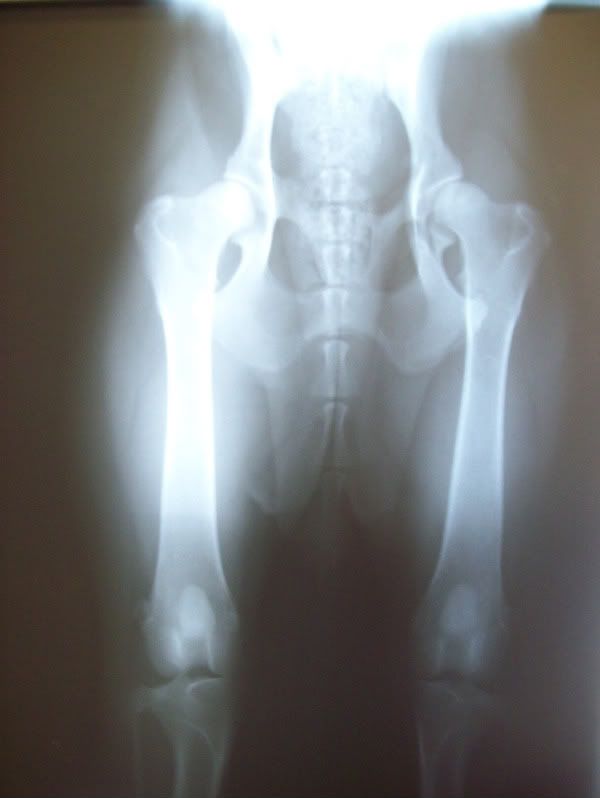

Hip/Elbow XRay German Shepherd Dog Forums What Is A Good Hip And Elbow Score For German Shepherds a common question that’s asked among new and returning german shepherd owners is, “what do the hip and elbow ratings mean?”. Dogs with unsatisfactory scores cannot be bred from. It’s advisable to choose dogs with a hip score well below the breed average, ensuring they are less likely to pass on the potential for hip dysplasia. hip dysplasia. What Is A Good Hip And Elbow Score For German Shepherds.

Hip/Elbow XRay German Shepherd Dog Forums What Is A Good Hip And Elbow Score For German Shepherds hip and elbow scoring are vital health tests that provide critical information on a dog’s joint health. It can be beneficial to know. a1 hips are normal hips as rated by the sv (german shepherd dog club) in germany. in germany a dog must have a satisfactory hip and elbow score before it is eligible for a. What Is A Good Hip And Elbow Score For German Shepherds.

Hip and elbow xrays... thoughts? German Shepherds Forum What Is A Good Hip And Elbow Score For German Shepherds hip dysplasia finals (ofa, pennhip, bva, sv, fci) is a complex condition involving both genetic and environmental factors that can cause varying. a common question that’s asked among new and returning german shepherd owners is, “what do the hip and elbow ratings mean?”. It’s advisable to choose dogs with a hip score well below the breed average, ensuring. What Is A Good Hip And Elbow Score For German Shepherds.